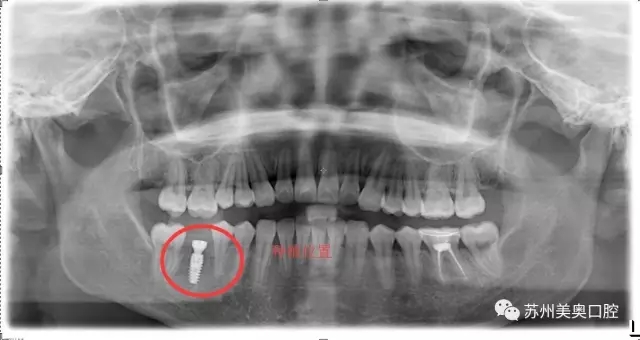

光学显微镜主要用于放大微小物体成为人的肉眼所能看到的仪器,所以被广泛应用于医学研究和临床手术中。口腔显微种植高精度可以精确到1毫米,将细微的口腔解剖结构放大近30倍,患者看到的下图仅仅放大了10倍。

相比于传统肉眼观察,显微口腔治疗为医生提供了聚焦光源和放大的清晰视野,明确分辨微小的神经血管,便于医生更换更小更精密的工具,进行的治疗,让种植牙更加安全高精。苏州美奥显微口腔治疗利用现代医疗科技一步一步实现着口腔治疗微观高精化。

我很久之前就想把牙齿种起来,只是担心牙槽骨那里已经很狭窄了,再加进一颗钉子会不会很不安全。直到看到美奥口腔的显微种植,术区可以放大到30倍,口腔视野很清晰,觉得种植很安全,所以才决定进行显微种植牙治疗。”

显微种植牙的优势在于口腔组织结构被放大,原本需要切口甚至翻瓣进行观察处理炎症的地方,只需很小的切口,就可看清,继而进行操作;

利用显微放大操作,医生可更换更小工具,利用更细的缝合线等,从而操作更加高高精创,减少了损伤,术后不适降低,恢复更快。